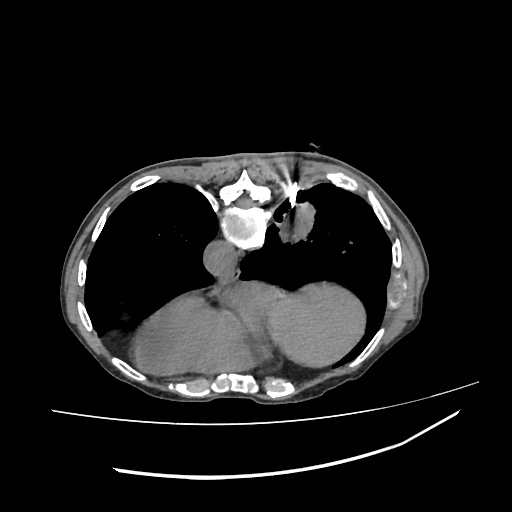

LUNG MASS BIOPSY, 45Y F

LUNG MASS BIOPSY, 70Y F

PANCRATIC BIOPSY, 34Y M